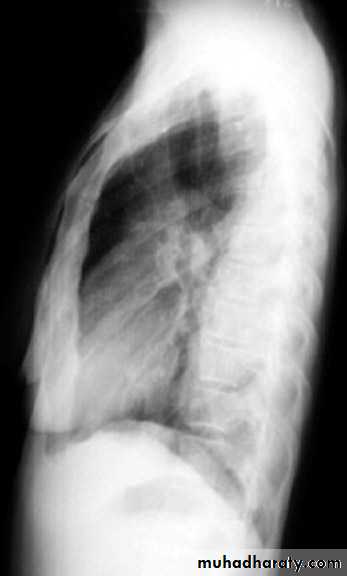

Middle lobe pneumonia

rt.upper lobe pn. Left lower lobe pn.